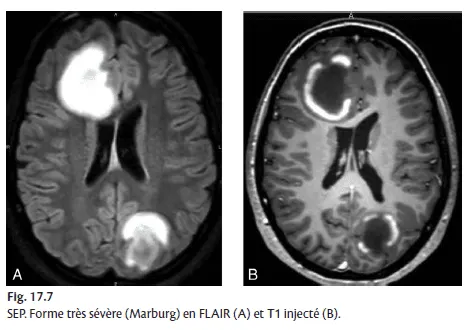

maladie de Marburg : multiples lésions et prises de contraste d'aggravation rapide, avec parfois atteinte des noyaux gris (fig. 17.7) ;

Figure 17.7